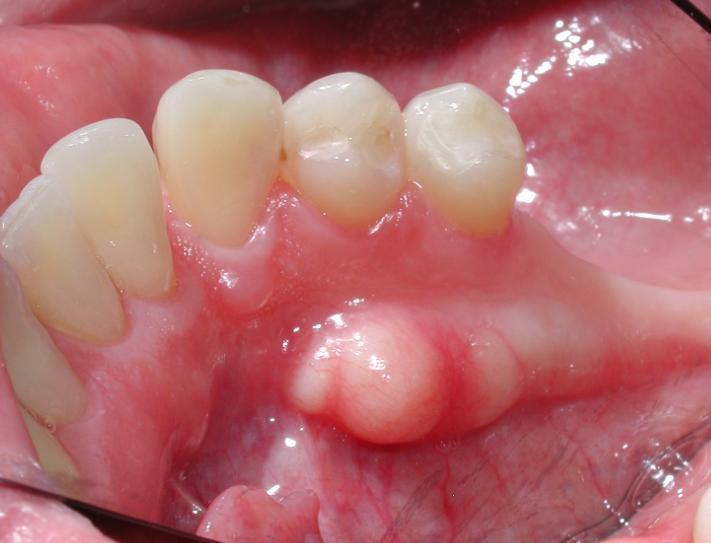

Ranula

A ranula presents as a fluid-filled cyst forming under the tongue, usually in the sublingual land (see Figure 7). It typically is a painless lump. A ranula usually is caused by a blocked salivary gland that becomes infected, although there may be other unknown causes. It also may appear white or bluish in color and cause difficulty in speaking, eating, or swallowing. A ranula usually is found during an oral examination by a dentist or physician and often requires a biopsy if there is a suspicion of cancer. Often, a small ranula may resolve itself gradually on its own.1,6,7,10

![]() |

Usually, the cyst and affected sublingual gland are surgically removed. A marsupialization procedure also can be performed, in which the cyst is opened and the edges are stitched to the inside of the mouth. This procedure allows it to drain. Most ranulas are successfully treated with conservative measures or surgery, and recurrence is less common after surgical removal. Ranulas are not contagious and are more common in children and young adults. The patient should avoid biting or puncturing a ranula, since this can lead to an infection. A ranula seldom goes away on its own untreated.6,7,10